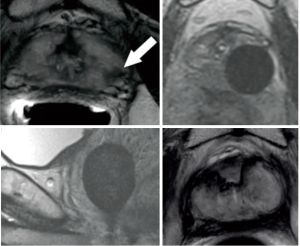

Thermoprotection of the rectal wall, used during cryosurgery, is achieved with a technic of hemo-dissection of the recto-prostatic space (6): we take 50 to 80 milliliters of patient’s blood from the humeral vein and we reinject it into the Denounvillier’s fascia under ultrasound guidance. MRI-control show that the hematoma moves the prostate away from the rectal wall (Figure 3).

Thermoprotection of the rectal wall during cryosurgery is achieved by a technique based on hemo-dissection of the recto-prostatic space (6): around 50 to 80 milliliters of patient’s blood is withdrawn from the humeral vein and is then injected into the Denounvillier’s fascia under ultrasound guidance. MRI-confirmed that creation of this hematoma moves away the prostate from the rectal wall (Figure 3).